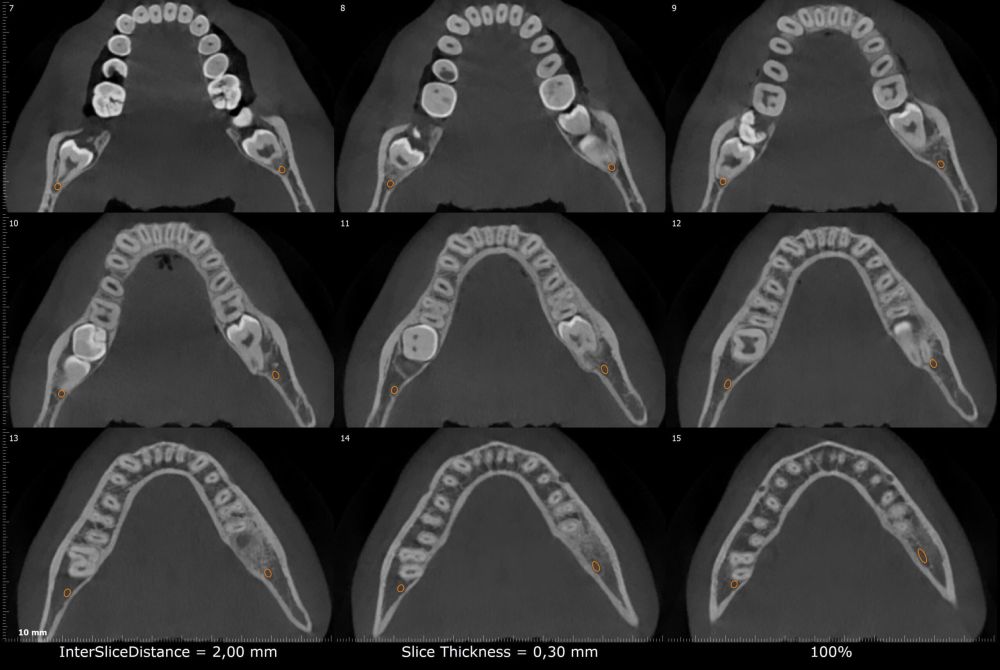

Métodos: Se presenta el caso clínico de un paciente varón de 18 años en el que, tras la realización de una CBCT de la arcada mandibular, se observó la retención de los segundos molares mandibulares permanentes junto con los terceros molares mandibulares.

Conclusiones: La retención del segundo molar mandibular es un hallazgo creciente en jóvenes y requiere un diagnóstico precoz para evitar complicaciones, siendo la CBCT la herramienta diagnóstica más precisa para evaluar la posición y riesgos asociados. Las opciones terapéuticas son diversas y siempre deben individualizarse según la anatomía, el pronóstico y las características del paciente.

Methods: We present the case of an 18-year-old male patient in whom, after performing a CBCT of the mandibular arch, retention of the permanent mandibular second molars was observed, along with the mandibular third molars.

Conclusions: Retention of the mandibular second molar is becoming more common in young patients and needs to be diagnosed early to avoid complications. CBCT is the most accurate tool to assess the tooth position and possible risks. Treatment options vary, and they should always be based on the patient’s anatomy, prognosis, and individual characteristics.